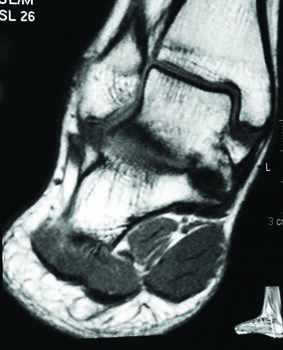

A tarsal coalition exists when there is a congenital, complete or incomplete union between two or more tarsal bones causing restricted motion or absence of motion. Tarsal coalitions remain challenging for the foot and ankle physician and surgeon. Their clinical hallmarks are primarily pain, rigid pes valgus and/or rigid pes planus deformity, and often tonic peroneal muscle spasm. Although the diagnosis of a tarsal coalition is often readily apparent upon clinical examination, diagnostic imaging is confirmatory and often aids in planning any necessary surgical intervention. Sequentially, the author always obtains radiographs of the involved foot first followed as necessary by advanced imaging with either computerized tomography (CT) or magnetic resonance imaging (MRI) scans, or in some instances of incomplete tarsal coalition, both CT and MRI.1

Recently, the literature presents arguments for the inclusion of the size and type of talocalcaneal coalition, and the degree of heel valgus as factors to consider when deciding between joint resection and joint fusion.3-11 Some hypothesize that the size of a talocalcaneal coalition inversely correlates with the success rate of resection, and some researchers used preoperative advanced imaging studies, particularly CT, to investigate.3,4 Arbitrarily, based only on their personal experience, these investigators concluded that talocalcaneal coalitions involving greater than 50 percent of the talocalcaneal joint are less amenable to surgical resection.3,4 More recently though, several authors challenged this subjective assumption and instead determined that no definitive talocalcaneal coalition size precludes an attempt at resection in every patient.5-7

Additionally, different described shapes and morphologies of talocalcaneal coalitions may be a factor to consider when debating arthroplasty or arthrodesis. In 2010, Rozansky and colleagues used thin-cut 2D and 3D CT scans to divide talocalcaneal coalitions into five different types based on their cartilaginous or bony nature, location and facet joint orientation.8 In 2016, Bixby and associates used CT scans to assess 97 patients with a total of 138 talocalcaneal coalitions.9 They found that 97 (70 percent) of the coalitions involved the middle facet, 39 (28 percent) the posteromedial aspect of the joint and two (1.4 percent) involved the posterior facet.9 They described the posteromedial talocalcaneal coalition as being associated with an intact, but shorter middle facet with a long sustentaculum tali.9